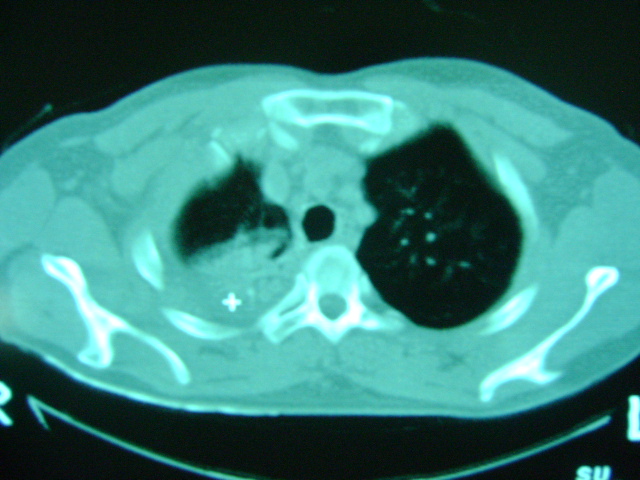

标题: CT16197:新手求教,M,42y,外伤入院,略感气紧,余无不适 [打印本页]

标题: CT16197:新手求教,M,42y,外伤入院,略感气紧,余无不适

肋骨骨折,肺挫伤,胸腔积液,不张?

肋骨骨折,右肺挫裂伤,右侧胸腔积液,没有气胸很奇怪啊

肋骨骨折,肺挫伤,胸腔积液,

肋骨骨折,肺挫伤,胸腔积液,左肺代偿性气肿.

肋骨骨折,肺挫伤,胸腔积血.

右侧肋骨骨折,右肺挫伤,右侧胸腔积液(血)。

肋骨骨折,肺挫伤,双侧胸腔积血.

右上肺后段片状实变影有点状钙化,左下肺亦可见结节影,应考虑结核